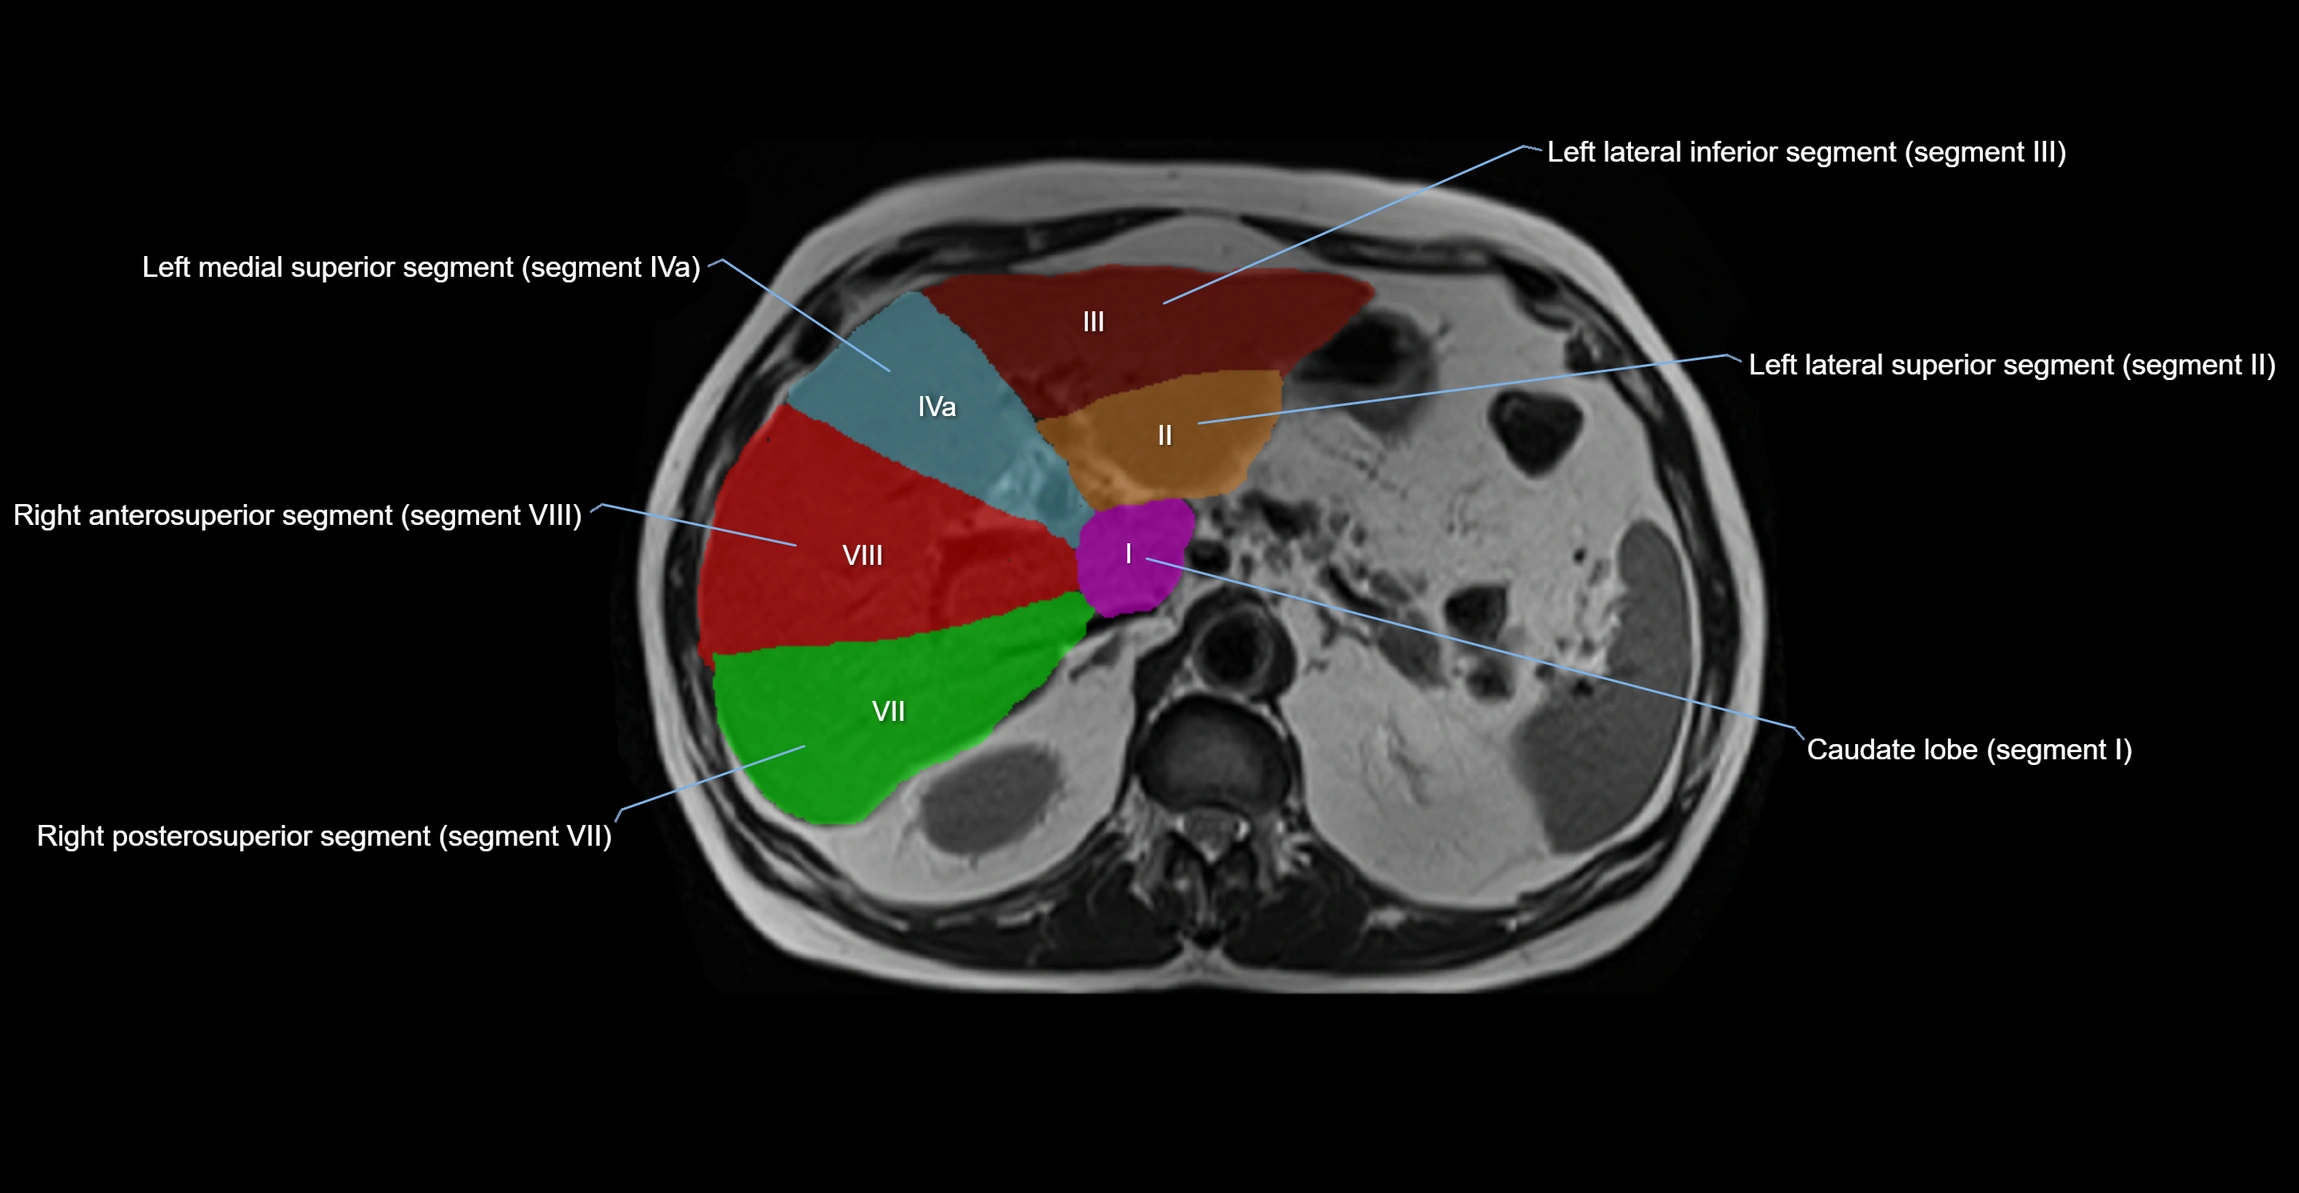

The caudate lobe of the liver is a distinct anatomical subdivision of the liver, designated as segment I in Couinaud’s classification. It lies on the posterior surface of the liver, between the fissure for the ligamentum venosum (left boundary) and the groove for the inferior vena cava (IVC) (right boundary). Superiorly, it is related to the posterior liver surface, and inferiorly it is separated from the left lobe by the porta hepatis.

The caudate lobe is unique because it receives dual portal venous and arterial inflow from both the right and left portal veins and hepatic arteries. It also has independent venous drainage directly into the IVC via multiple small hepatic veins, unlike other lobes that drain through the three main hepatic veins.

This anatomical autonomy makes the caudate lobe especially significant in liver surgery, transplantation, and hepatic venous outflow obstruction syndromes (e.g., Budd–Chiari syndrome). Enlargement of the caudate lobe is a characteristic imaging feature in chronic liver disease and cirrhosis.